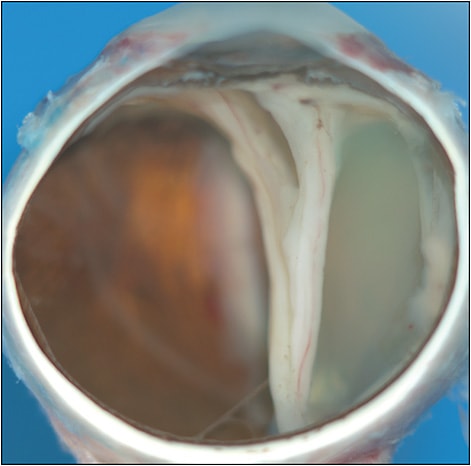

Delayed-onset RD may also occur in “end-stage” disease, marked by phthisis bulbi and corneal opacity (Figure 3). Histopathology of a series of eyes enucleated for refractory pain following Streptococcus mitis endophthalmitis demonstrated RD in all 5 specimens.5 In many instances, it may be preferable to elect observation over further surgical attempts to repair these complex RDs. In the largest study of RD associated with endophthalmitis, 65.2% (289/443) were classified as “inoperable” due to no light perception, phthisis bulbi, or “very poor visual prognosis.”1